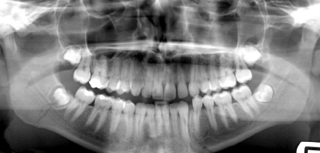

Any supporting material like photographs and x-rays you feel relevant can be submitted for any patient prior to case review acceptance by us.

However it is expected you have examined the patient, examined all the records and noted any relevant details and concluded the patient is in good oral health and a suitable candidate for Aligner Therapy.

Some common issues to tell us about may be periodontal conditions,restorations,

implants veneers, root morphology, root resorption and ankylosed teeth.